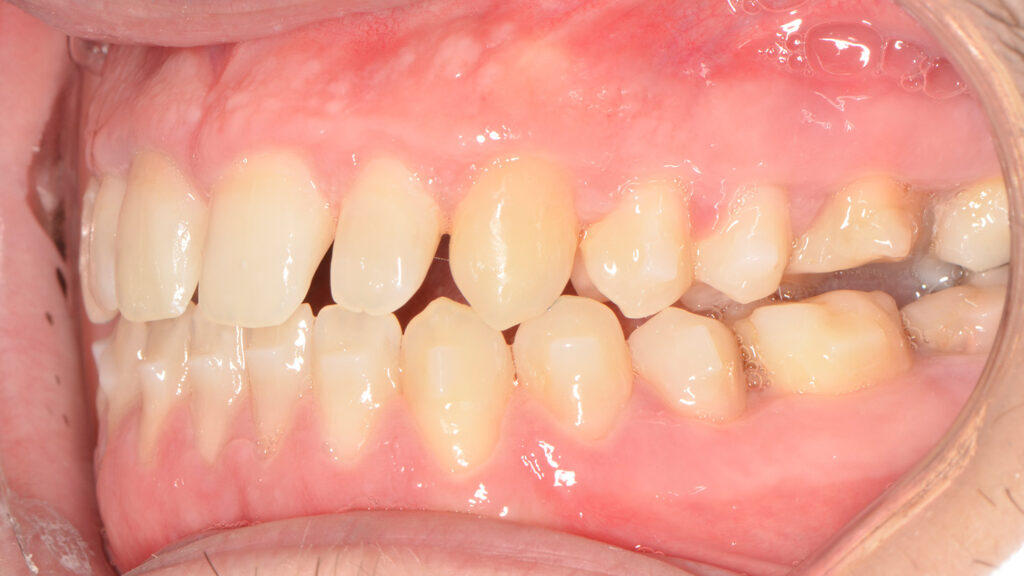

Intraoral examination showed an Angle Class III relationship on both sides, along with an anterior open bite. Additionally, a narrow maxilla with a bilateral posterior crossbite was observed.

For sagittal correction, a new set of aligners made from Trugen XR™ material was fabricated. The corono-distal tipping of the premolars in the fourth quadrant was corrected using intermaxillary elastics.

Ultimately, we successfully corrected the crossbite, open bite, and Class III canine relationship. The patient rehabilitated tooth #26 with an on lay and tooth #47 with an implant, resulting in a stable occlusion. Post-treatment retention involved a fixed retainer in the lower arch and removable retainers for both upper and lower arches to maintain the treatment results.